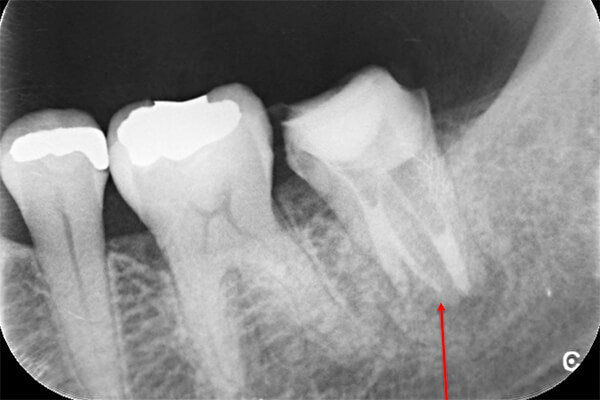

①自覚症状なし・歯肉にサイナストラクト(排膿路)あり

②初診時レントゲン解説

・歯根周囲に透過像(黒い影)あり

・遠心根根管充填:アンダー

根管治療そのものは、2回で終了し、水酸化カルシウム貼薬し経過観察(患者様希望のため)

約2か月後、根尖透過像の縮小を確認し根管充填(MTA使用)。

レントゲン解説:4根管すべてに根管充填が密にされていることを確認できる

透過像は消失し、明らかな骨形成を認める。(黒い影の消失)